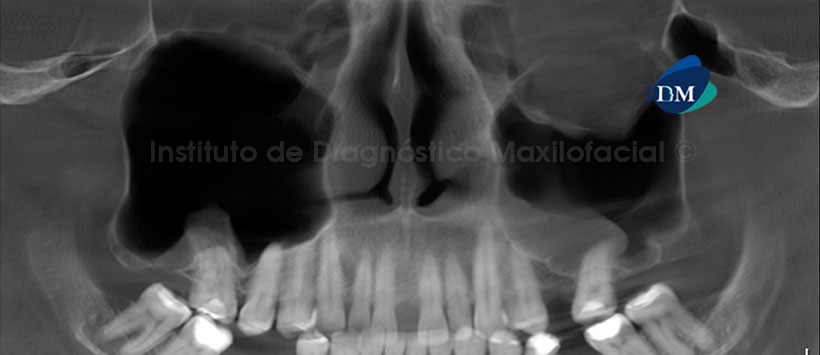

A la evaluación de la reformación panorámica de la tomografía volumétrica (CBCT) se aprecia descenso del globo ocular izquierdo y engrosamiento de la mucosa a nivel del piso del seno maxilar izquierdo. (Figura 1)

A la evaluación la CBCT en cortes axiales (Figura 2), coronales (Figura 3) y sagitales (Figura 4). Se aprecia fractura polifragmentaria que compromete el reborde supraorbitario y el techo orbital del lado izquierdo así mismo se evidencia las secuelas de la disyunción de las suturas frontocigomatica y cigomática temporal. Además se evidencia el compromiso del piso de orbita asociado al descenso del globo ocular. Por otro lado se aprecia discontinuidad de la pared lateral del seno maxilar del mismo lado, Además de la neumatización y el engrosamiento de la mucosa de ambos senos maxilares a predominio del lado izquierdo.